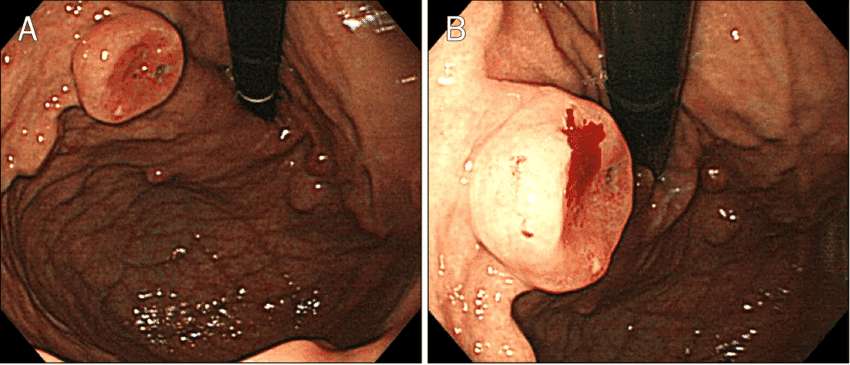

۱. پولیپهای هایپرپلاستیک (Hyperplastic Polyps)

اینها شایعترین نوع پولیپهای معده هستند و اغلب در افرادی که دچار ورم معده (گاستریت) ناشی از عفونت هلیکوباکتر پیلوری هستند، دیده میشوند. پتانسیل سرطانی شدن آنها بسیار پایین است.

-درمان پولیپ هایپرپلاستیک:

درمان علت زمینهای: قدم اصلی، درمان عاملی است که باعث التهاب شده. اگر عفونت هلیکوباکتر پیلوری وجود داشته باشد، درمان آن با آنتیبیوتیک اغلب باعث کوچک شدن یا از بین رفتن کامل این پولیپها میشود.

برداشتن پولیپ (پولیپکتومی): پولیپهای هایپرپلاستیک بزرگتر از ۱ سانتیمتر باید در حین آندوسکوپی برداشته شوند، زیرا احتمال دیسپلازی (تغییرات پیشسرطانی) در آنها کمی بیشتر است. پولیپهای کوچکتر معمولاً فقط تحت نظر گرفته میشوند.